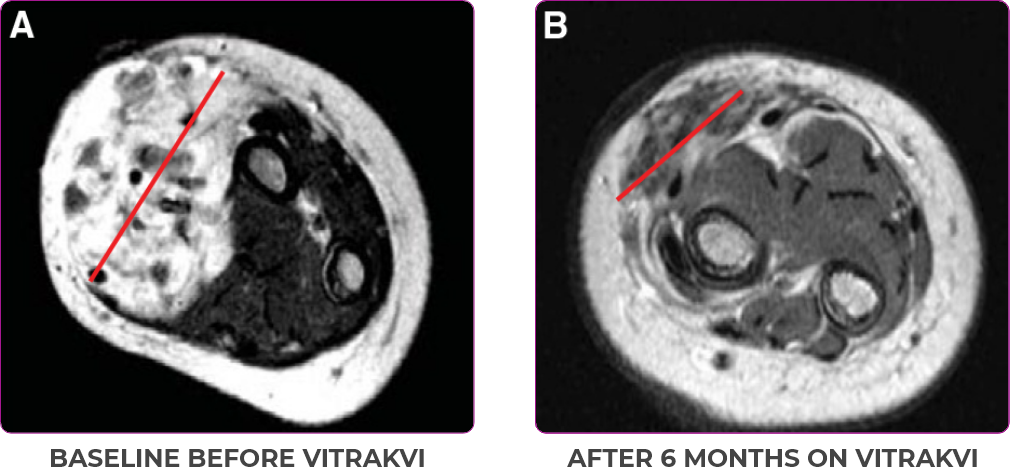

Reduction in tumor burden1

MRIa imagery of the brain. Red line indicates the maximum dimension.1

aMRI, magnetic resonance imaging.

Pre- and post-treatment imaging, by DuBois SG et al, is licensed under CC BY 4.0.

- Patient achieved a confirmed partial response after 4 cycles of VITRAKVI with a 45% reduction in tumor burden

- Following 6 cycles of VITRAKVI, the patient was referred for definitive limb-sparing surgery

- Pathology revealed a complete pathologic response and clear resection margins with scar tissue noted